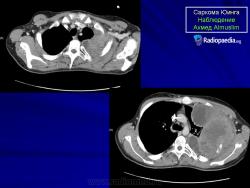

С Радиопедии.

Саркома Юинга грудной стенки.